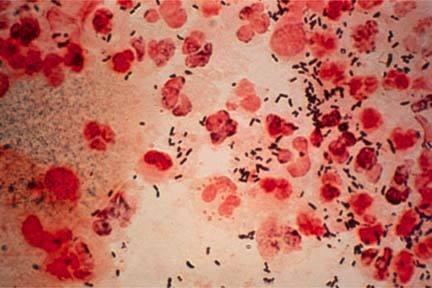

淋病是由淋球菌引起的一种泌尿生殖系统的化脓性感染,也包括眼、咽、直肠、盆腔和播散性淋球菌感染。属中医淋证、淋浊的范畴,本病病原体为淋病奈瑟菌或称淋病双球菌,为革兰氏染色阴性的双球菌,只能感染人,离开人体不易生长。